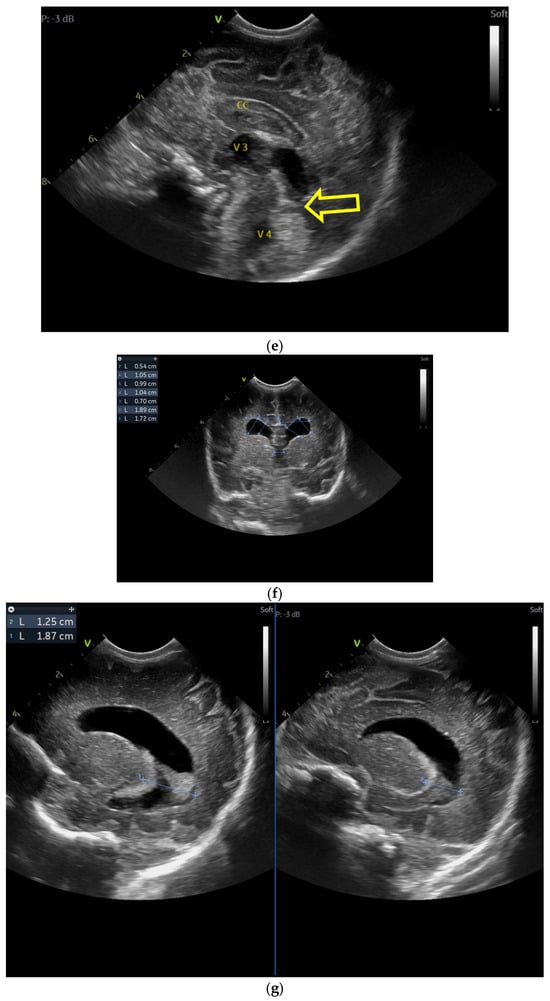

The first CUS was performed 24 h after birth and showed dilation of the third and fourth lateral ventricles, enlargement of the Sylvius aqueduct, and the presence of an arachnoid cyst (Figure 3a–e).

Figure 3.

(a) Cranial ultrasound. Coronal view. Enlargement of the lateral ventricles with hyperechoic and third ventricle dilation. D1, D2—Levine index measurement. D3, D4—anterior horn width measurement. D5—third ventricle (personal image collection). (b) Cranial ultrasound. Sagittal view. Up—left ventricle. D1, D2—lateral ventricle measurements and thalamo-occipital horn width. Down—right ventricle. D1, D2—lateral ventricle measurements and thalamo-occipital horn width (personal image collection). (c) Cranial ultrasound. Sagittal view. Up—enlargement of the third and fourth ventricles. Measurements of the ventricles. Down—measurement of the resistive index (RI) performed on the anterior cerebral artery (ACA) using Doppler flow measurements. RI—0.74 (personal image collection). (d) Cranial ultrasound. Transtemporal view. Yellow arrow—enlargement of the Sylvian aqueduct (personal image collection). (e) Cranial ultrasound. Sagittal view. Yellow arrow—arachnoid cyst posterior to the third ventricle (personal image collection). (f) Cranial ultrasound. Coronal view. Lateral ventricles and third ventricle enlargement. D1, D2—Levine index measurement. D3, D6—right lateral ventricle measurement (anterior horn width). D4, D5—left lateral ventricle measurement (anterior horn width) (personal image collection). (g) Cranial ultrasound. Sagittal view. Left—left ventricle. D1—thalamo-occipital distance measurement. Right—right ventricle. D2—thalamo-occipital distance measurement (personal image collection). (h) Cranial ultrasound. Coronal view. Up—orange arrow—third ventricle. Red arrow—fourth ventricles. Yellow arrow—arachnoid cyst. Down—resistive index measured on the anterior cerebral artery. RI—0.79 (personal image collection). (i) Cranial ultrasound. Transversal view. Up—RI precompression value on the middle cerebral artery performed with Doppler examination. RI—68. Down—RI post-compression value on the middle cerebral artery performed with Doppler examination. RI—0.79 (personal image collection). (j) Cranial ultrasound. Up—coronal view. L1, L2—Levine index measurement of the lateral ventricles. Down—sagittal view. L1, L2—measurement of the thalamo-occipital distance (personal image collection). (k) Cranial ultrasound. Sagittal view. L1, L2—measurement of the third ventricle. L3, L4—measurement of the fourth ventricle. L5, L6—measurement of the arachnoid cyst (personal image collection). (l). Head circumference-for-age. “X” symbols represent the measurements performed from birth and follow-up examinations. Head circumference was still under the curve during follow-up examinations (personal image collection) [28].

The CUS examination performed at 48 h after birth showed increases in the diameters of all ventricles. The resistive index presented an increase as well. The bregmatic fontanelle started bulging. The dimensions of the Sylvian aqueduct were not modified (Figure 3f–h).

The CUS examinations performed at four days and seven days after birth showed stabilization regarding the values of the diameters. The pre- and post-compression values of the resistive index of the middle cerebral artery showed a delta-RI of 0.11 (pre—0.68, post—0.79, Figure 3i).

After discharge, at three weeks after birth (follow-up examination), the ventricle measurements showed wider ventricles and the arachnoid cyst was still present (Figure 3j,k).

The next follow-up examination performed a week later showed a delta-RI of 0.12 and an increase in the cranial perimeter (+ one cm since the last follow-up).

At 12 weeks of life (five week corrected age), ventricle dilations were still present. Neurological examinations showed axial and limb hypotonia. The general movement examination showed a poor repertoire with a General Movement Optimality Score (GMOS) of 19. At 18 weeks of life (11 week corrected age), the neurological exam revealed that the infant presented plagiocephaly and could keep eye contact, and during the traction-to-sit maneuver showed hypotonia of the neck muscles. In the prone position, the infant was unable to hold the head up. The passive tone assessment showed the “scarf sign”, with the elbow at the midline bilaterally and a popliteal angle of 90° on the right and 110° on the left. Deep tendon reflexes were present. The general movement (GM) assessment revealed absent fidgety movements, with a Motor Optimality Score (MOS) of 13.